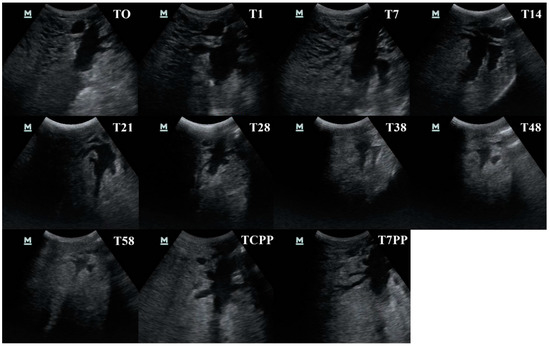

2.3. Ultrasonographic Examination of the Udder

2.4. Ultrasonographic Images Evaluation

3.2. Udder Cistern Size

3.4. Evaluation of the Ultrasonography Images